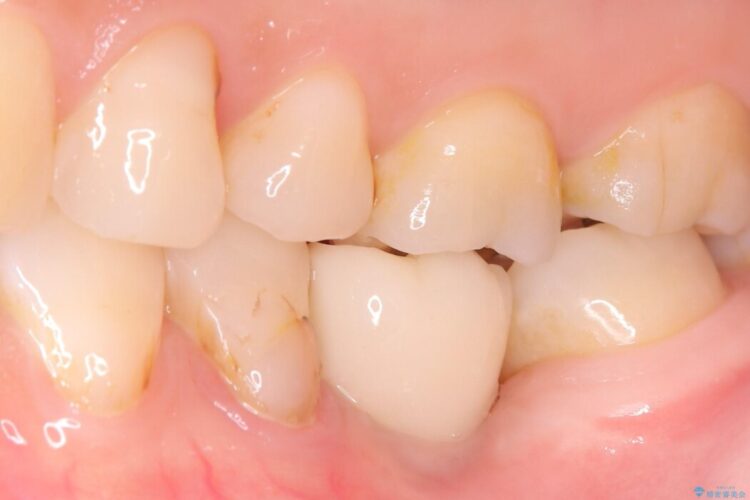

一般的に、骨が少ない場所への埋入は高度な技術を要しますが、今回は適切なサイズ(8.5mm)を選択し、埋入する深さを緻密にコントロールすることで、周囲の神経や重要な組織を傷つけることなく安全に処置を完了しました。

現在はインプラントが骨としっかり結合し、被せ物を装着して力強く噛めるようになっています。長期間の放置によって低下していた咀嚼機能が回復し、「もっと早く相談すればよかった」と喜んでいただけました。